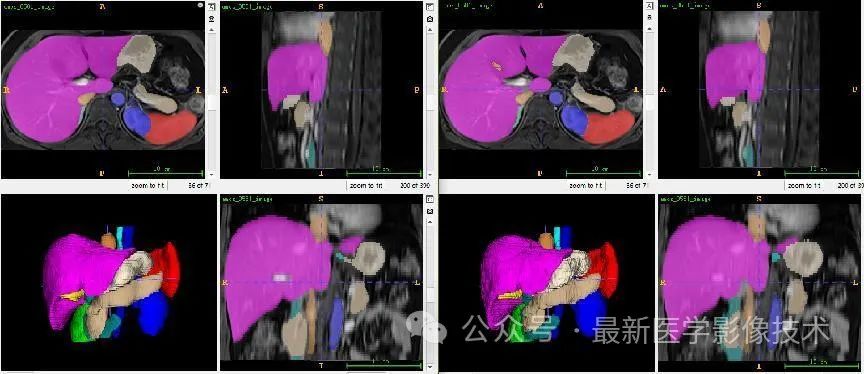

6、验证集分割结果

左图是金标准结果,右图是预测结果。